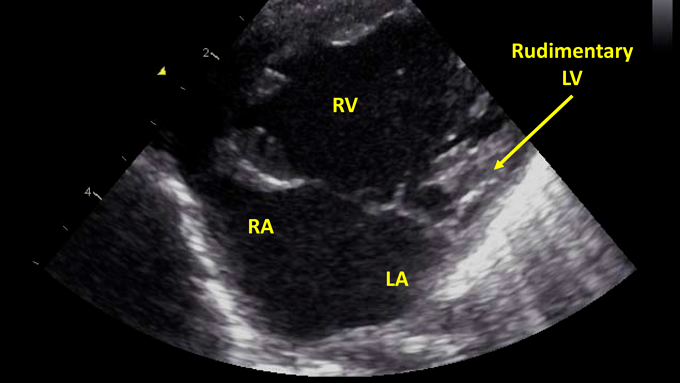

Fig. 3 Echocardiography after birth reveals hypoplastic left heart syndrome with mitral atresia and aortic atresia

LA, left atrium; LV, left ventricle; RA, right atrium; RV, right ventricle

胎児心エコー所見と同様,心室中隔欠損を合併した非典型的左心低形成症候群(僧房弁閉鎖,大動脈弁閉鎖)と診断した(Fig. 3).上行大動脈径は5 mmで,上行大動脈の血流は動脈管を介して逆行性に維持されていた.卵円孔は2 mm大で開存していたが狭小であり,左右短絡の通過血流速度は2.0 m/sであった.しかし,胎児心エコー検査でみられた中等度の三尖弁逆流は認めず,大動脈基部から右房へ短絡する連続性の血流を認めた(Fig. 4, Movie B).右室の収縮能は良好であった.